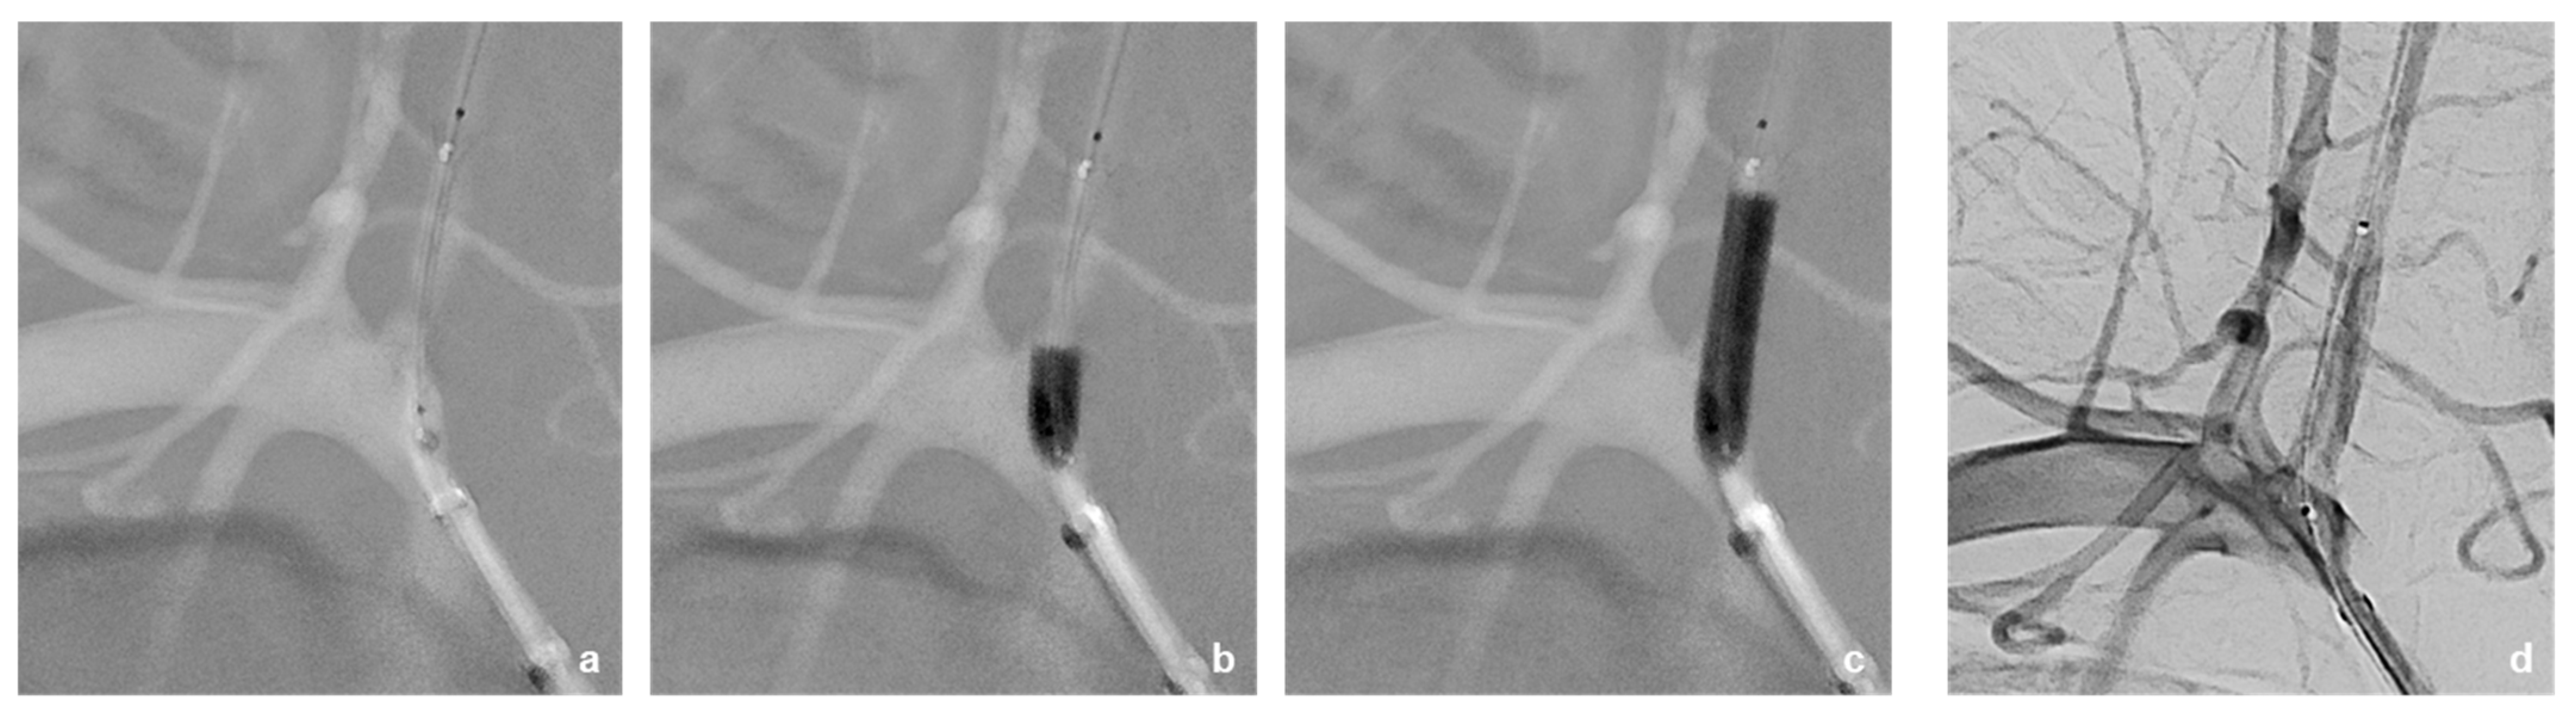

3.2. Neurointerventional Procedure

3.4. Postinterventional Result